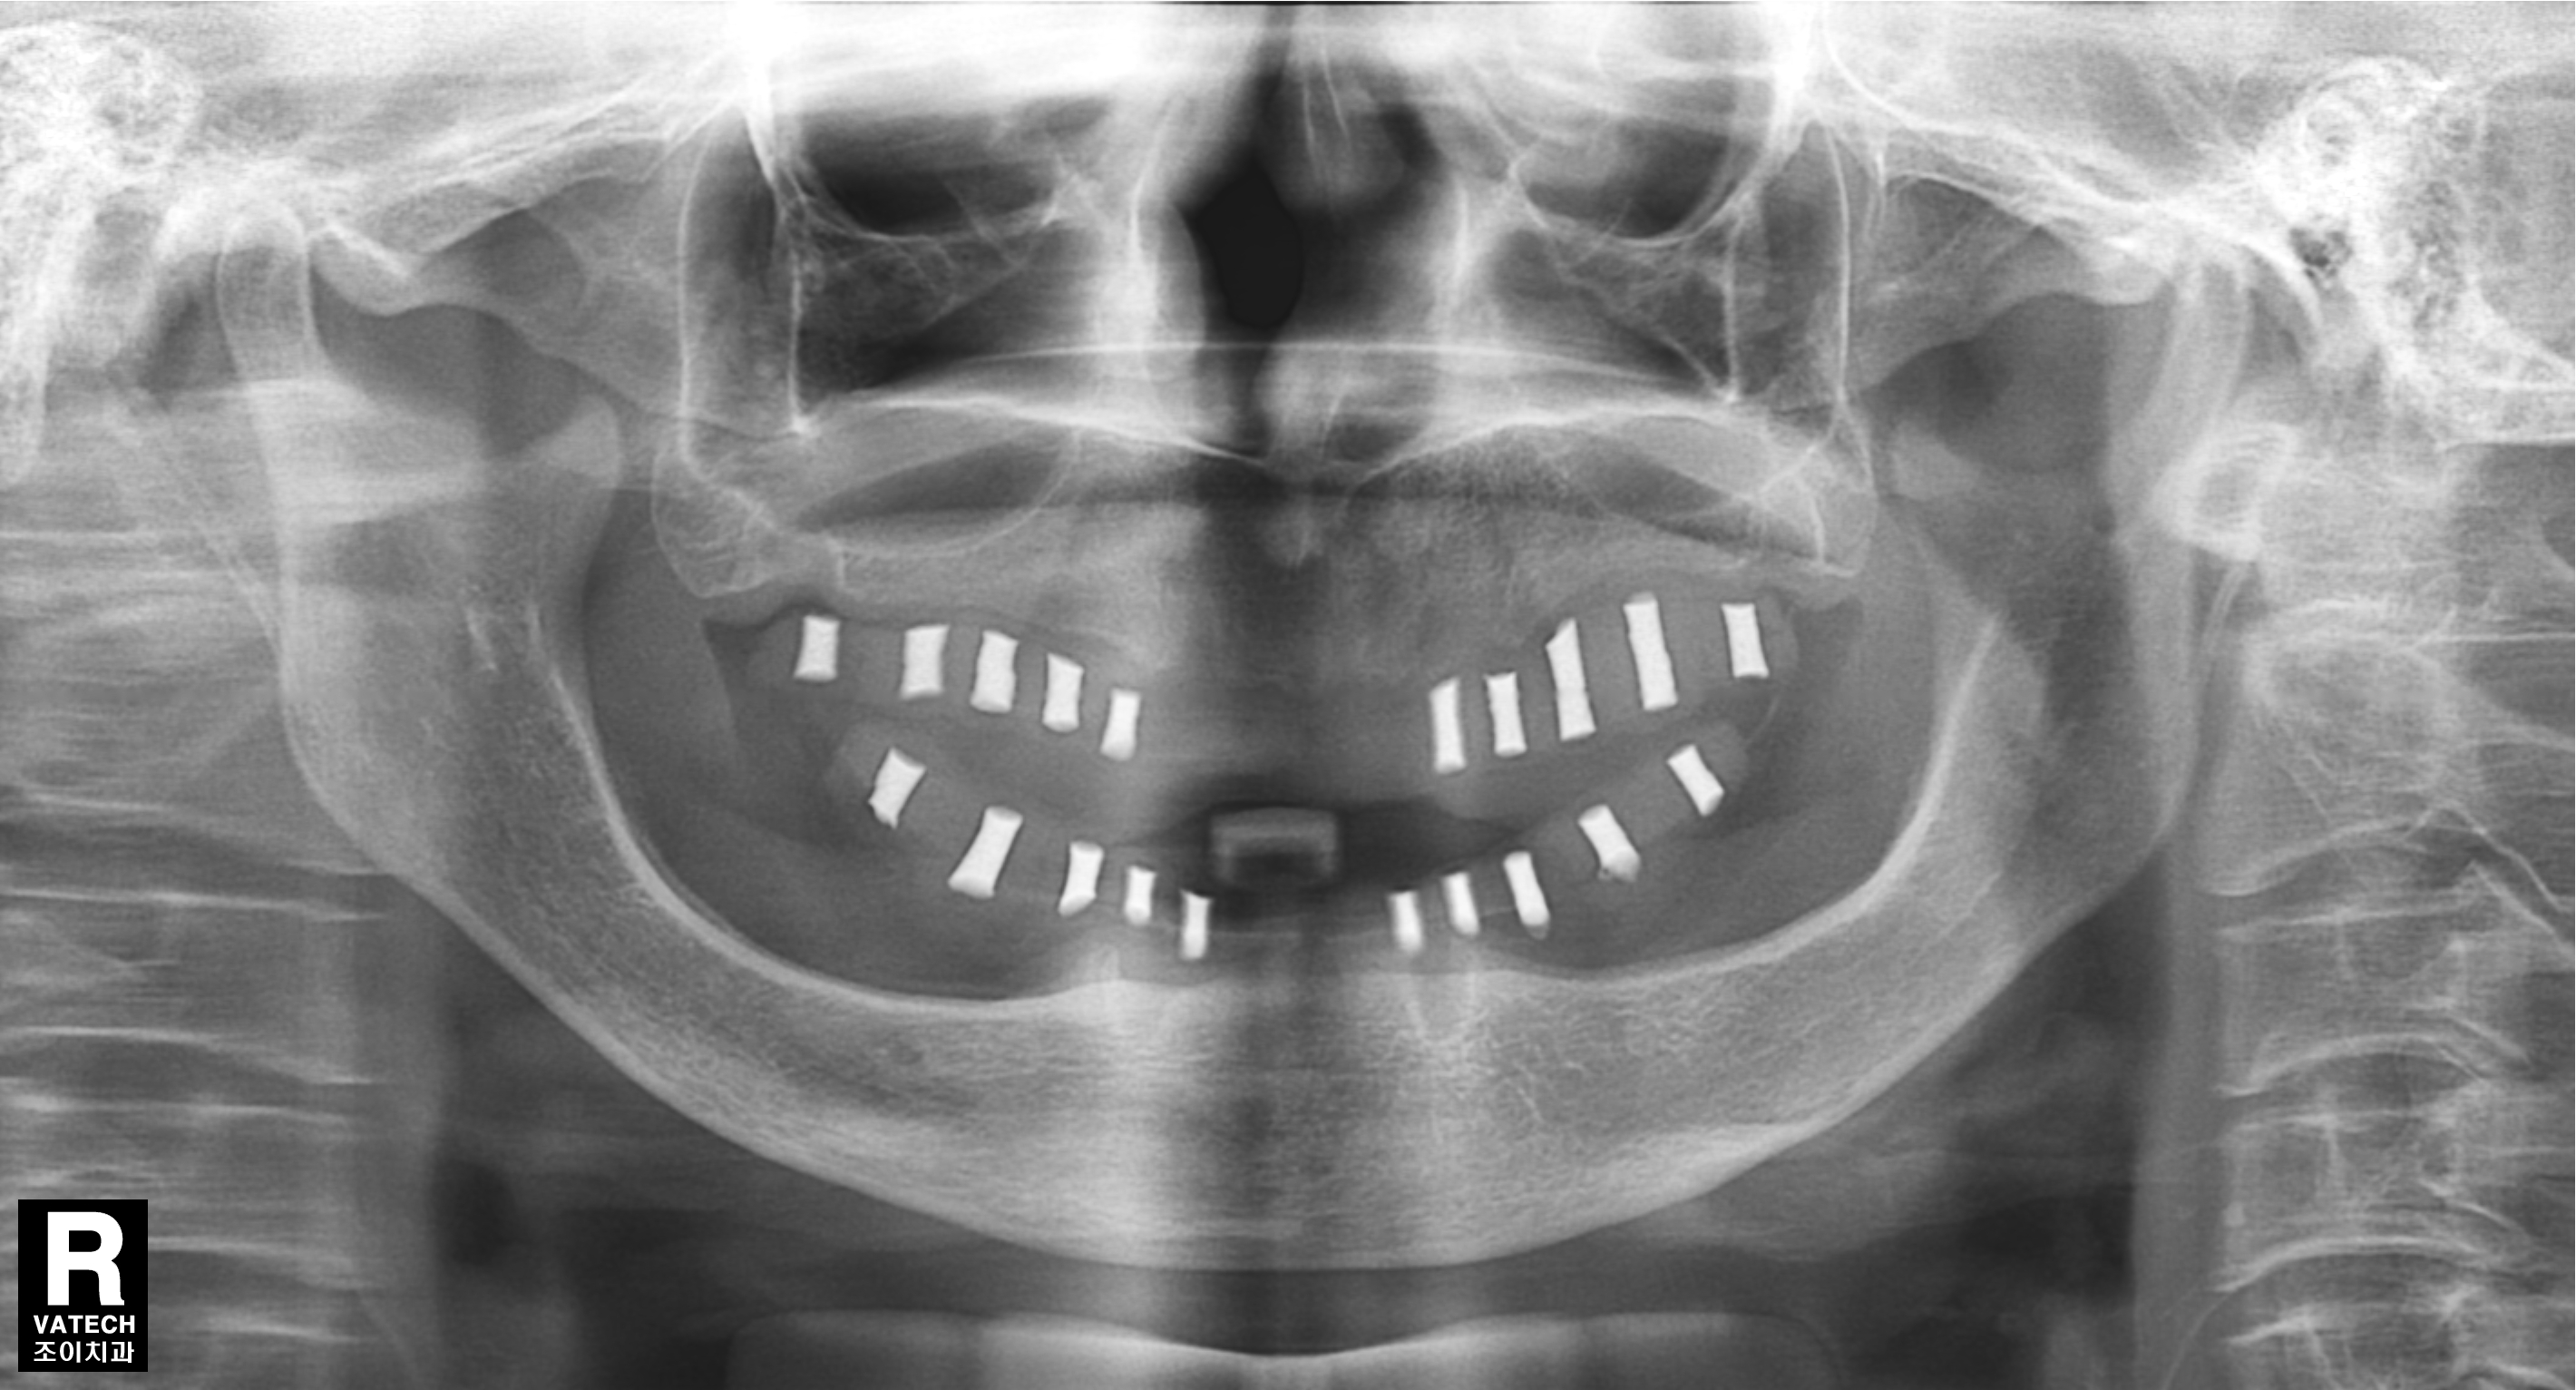

[임플란트] 제목 : 어테치먼트를 이용한 틀니치료

오래된 틀니 사용으로, 골흡수가 심하게 진행된 고령의 무치악 환자에서 어테치먼트를 이용한 틀니치료